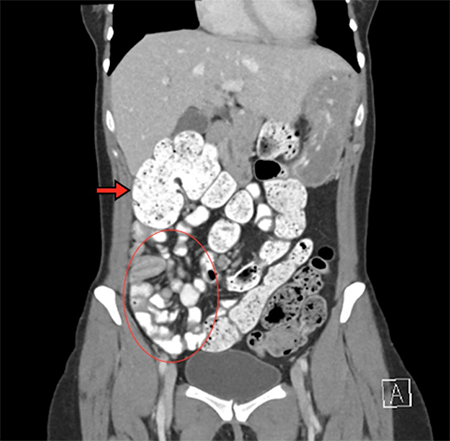

The patient, a 37-year-old woman, presented to the emergency department with four days of worsening abdominal pain. The pain was initially periumbilical in location, subsequently migrating to the right hemi-abdomen. The patient had had a longstanding history of nonspecific abdominal pain that had been labeled as irritable bowel syndrome by her primary care physician. The patient’s symptoms had been investigated seven years prior with an upper gastrointestinal contrast series. Per the patient, the study revealed "twisting" of her bowel, although no intervention was pursued at that time. She endorsed multiple loose bowel movements per day at baseline, but none since the onset of the acute pain. Vital signs were normal upon presentation, and examination revealed a soft, mildly distended abdomen, moderately tender to palpation in the epigastrium and right upper quadrant. Laboratory examinations were unremarkable. Given the patient’s tenderness on exam, a CT scan of the abdomen was performed which demonstrated the cecum abnormally positioned in the anterosuperior abdomen with multiple loops of small bowel displaced into the right lower quadrant (Figure 1). The duodenum did not clearly cross midline, the superior mesenteric vein (SMV) was seen to the left of the superior mesenteric artery (SMA), and swirling was seen in the small bowel mesentery (Figure 2).

Figure 1. The cecum is abnormally displaced in the right upper quadrant (arrow), with a significant amount of small bowel clustered to the right lower quadrant (circle).